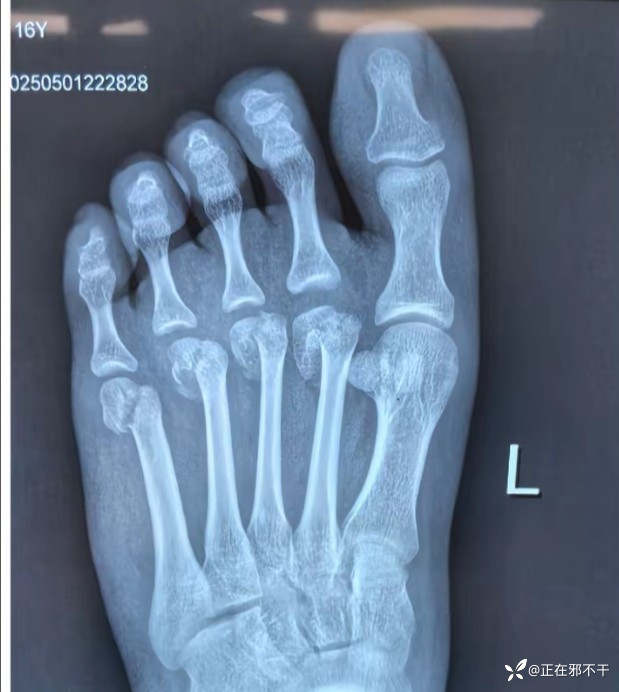

【患者信息】:女,16岁。

【主诉】:骑电动车摔伤之后导致左侧足部疼痛骨折。

【检查】:足部正侧位x光片

左足第二到第五跖骨远端骨折。

【临床诊断】:左足第二到第五跖骨远端骨折